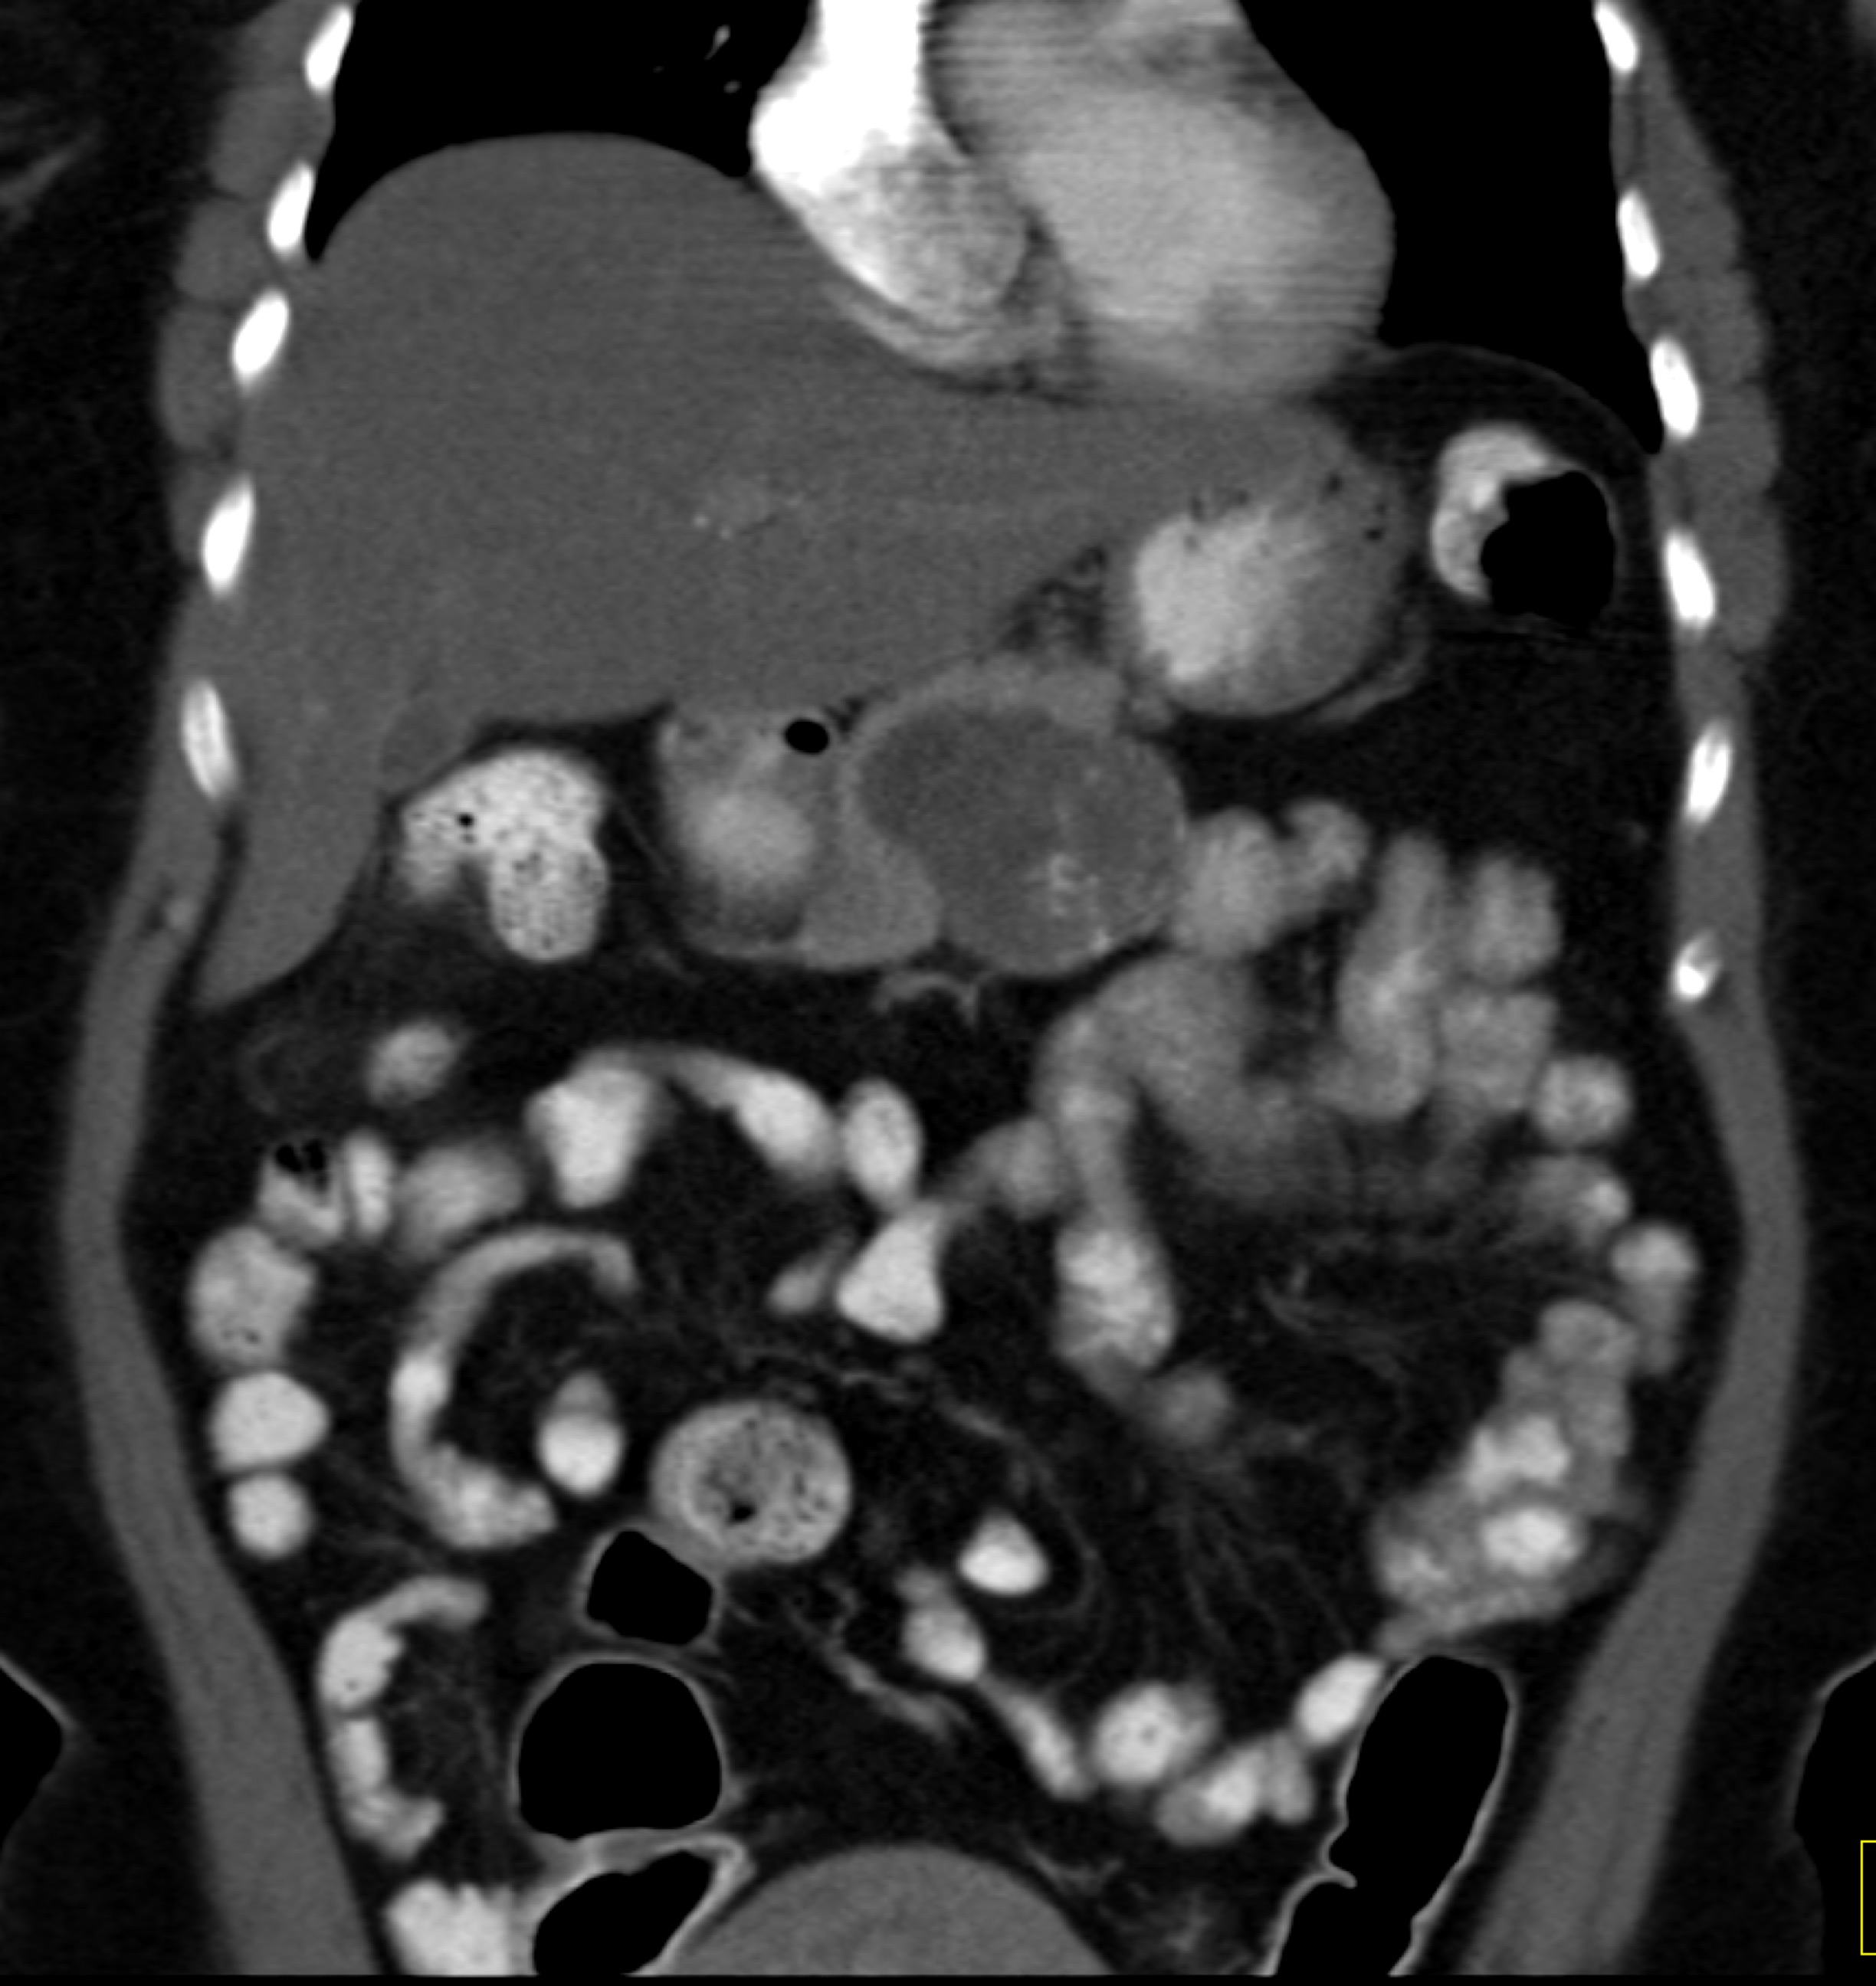

9) The best diagnosis in this 30ish year old female is?

renal cell carcinoma

MEST tumor (mixed epithelial and stromal tumor)

Wilms tumor

polycystic kidney disease